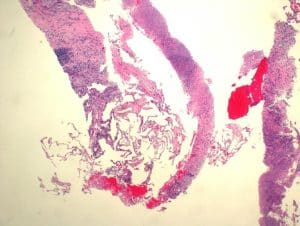

The patient had an unintentional 16 lb weight loss over the past year.  A referral to pulmonology was made, and the patient had an endobronchial ultrasound-guided biopsy completed. Three days after his biopsy, he presented to the emergency room with complaints of chest pain, vitals otherwise normal, and was found to have a non-ST elevation myocardial infarction requiring balloon angioplasty and stent placement to the left anterior descending artery. While in the hospital, infectious disease was consulted given left lung mass and biopsy findings showing chronic inflammation, extensive necrosis, gram stain positive for rare fungal hyphae, positive acid-fast bacilli (AFB), without any evidence of malignancy.

Figure 3: Hematoxylin and eosin stain of residual benign lung alveolar tissue and surrounding fibrous stroma with chronic inflammation and extensive necrosis with no evidence of malignancy seen (10x, scale bar 500 lm)

Figure 4: Extensive necrosis with no residual epithelium in this field. (5x, scale bar 500 lm)